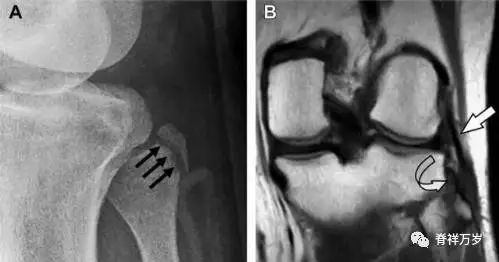

11Segond 骨折

Segond 骨折是发生在胫骨平台外侧的垂直撕脱性骨折(图 4)。这种骨折在前后位 X 线片上显示最佳。

屈曲位时膝关节受到内旋*力暴**作用,导致皮质骨撕脱性骨折,这种骨折常发生在运动员身上。常引起股骨内髁和胫骨平台后内侧骨挫伤,75%~100% 的患者伴前交叉韧带断裂,33% 的患者伴外侧半月板损伤。

图 4 一位足球运动员的 Segond 骨折

A 正位片示关节线下方胫骨外侧皮质撕脱(箭头)。B MRI 冠状位 T1 加权像示附着于髂胫带的骨折碎片(空箭头)。